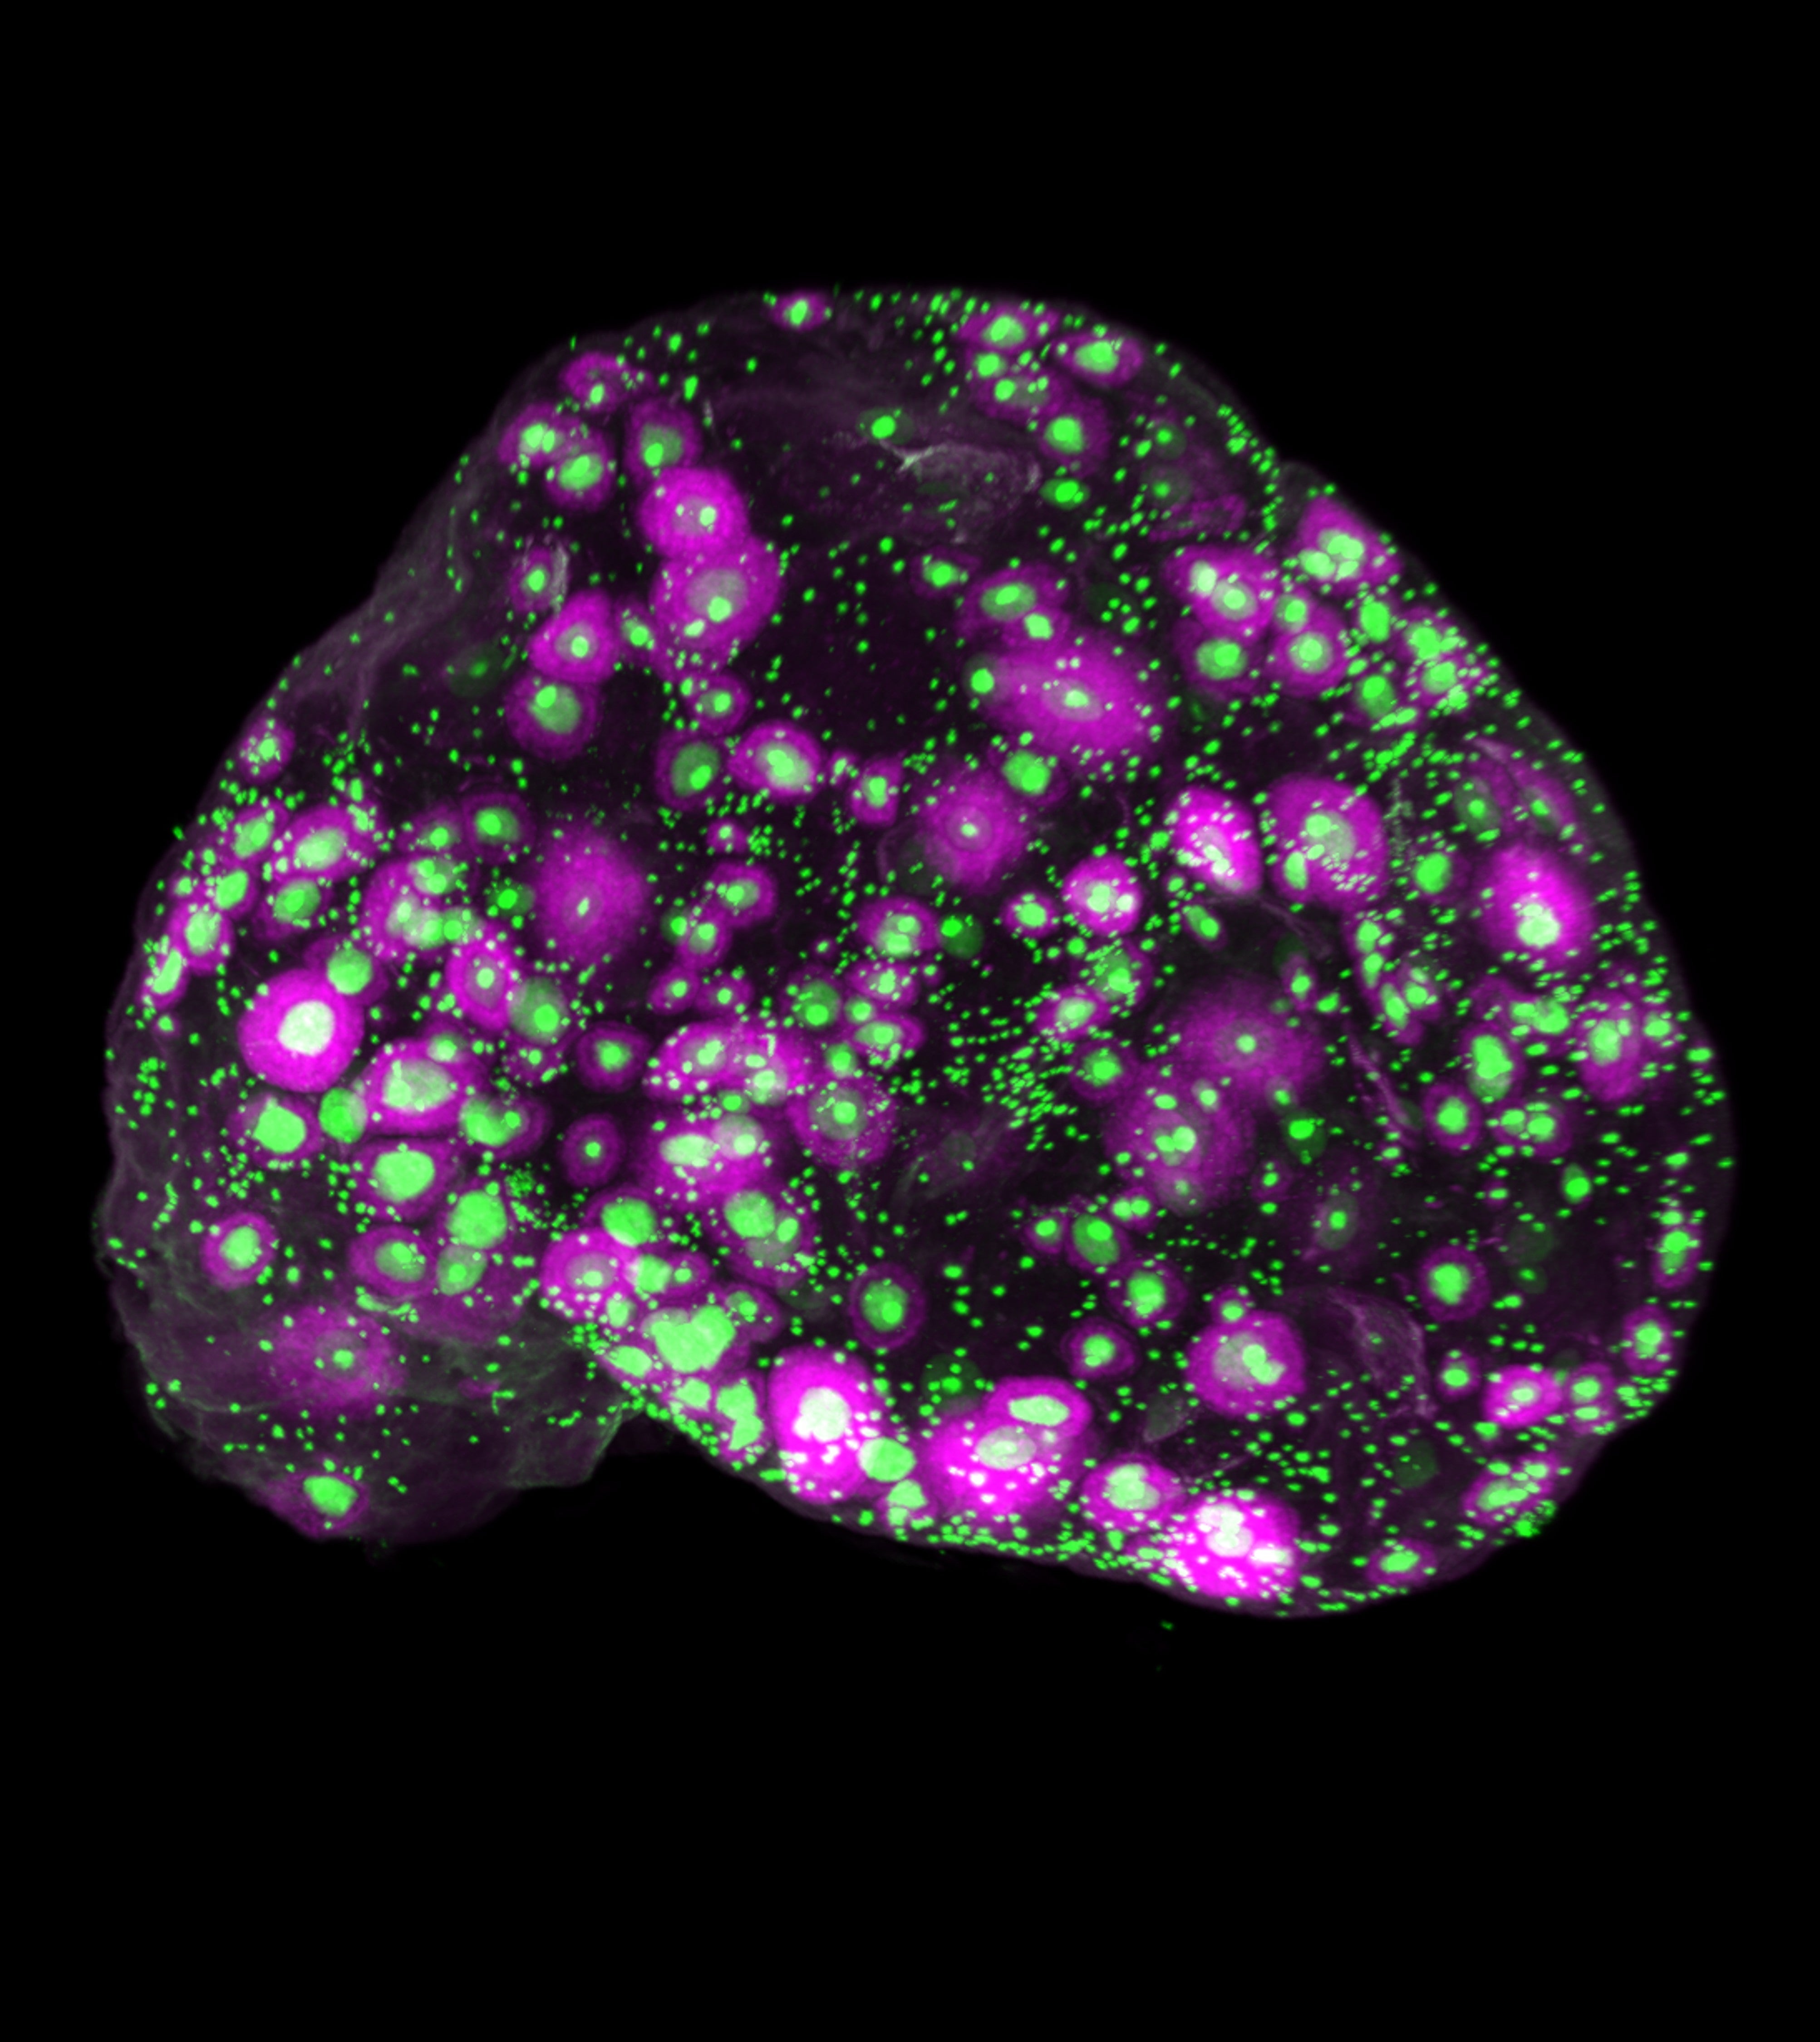

Gracias a una nueva tecnología de imagen, este equipo ha podido ver cómo es el envejecimiento normal en los ovarios de ratones y humanos.

Primero, desarrollaron una nueva técnica de imágenes en 3D que les permitió visualizar los óvulos en los ovarios sin tener que cortar los órganos en capas finas, como se hacía anteriormente.

Cuando ampliaron las imágenes 3D a ovarios humanos, descubrieron un hallazgo que los óvulos no se distribuyen uniformemente por el ovario. En cambio, se agrupan en «bolsas» rodeadas de zonas sin óvulos. Con la edad, la densidad de óvulos en estas bolsas disminuye.

«Fue una sorpresa; supusimos que los óvulos se distribuirían de forma más uniforme según lo que observamos en el ovario en desarrollo», asegura Laird. Explica que «esas bolsas sugieren que, incluso dentro de un mismo ovario, el entorno que rodea a un óvulo puede influir en su duración y en su maduración».